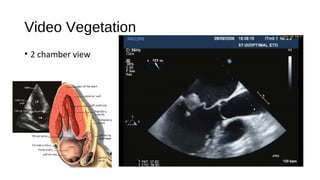

Video Vegetation

• 2 chamber view